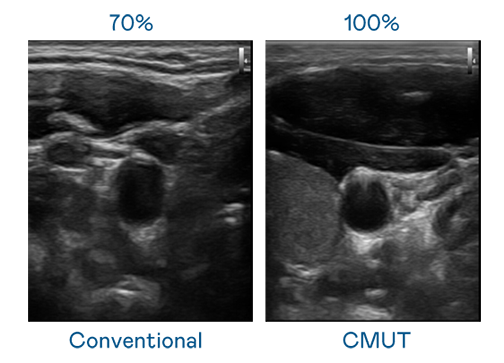

CMUT 技术是一种用电容式微机电元件来产生超音波讯号的技术。与传统 PZT 压电式技术相比,CMUT 频宽增加 30%,更宽频的超音波讯号让影像解析度大幅提升,是实现高影像品质医疗超音波扫描、促进精准医疗发展的关键技术。

大频宽带来超清晰影像

超音波影像的解析度高低,首先取决于探头能发出的讯号频宽。rb88随行版 CMUT 可提供高清晰的超音波讯号,提供高频宽、高灵敏度、影像纹理细节更高的超音波影像,协助医护人员缩短影像判读时间及利用精准的医疗影像进行诊断。